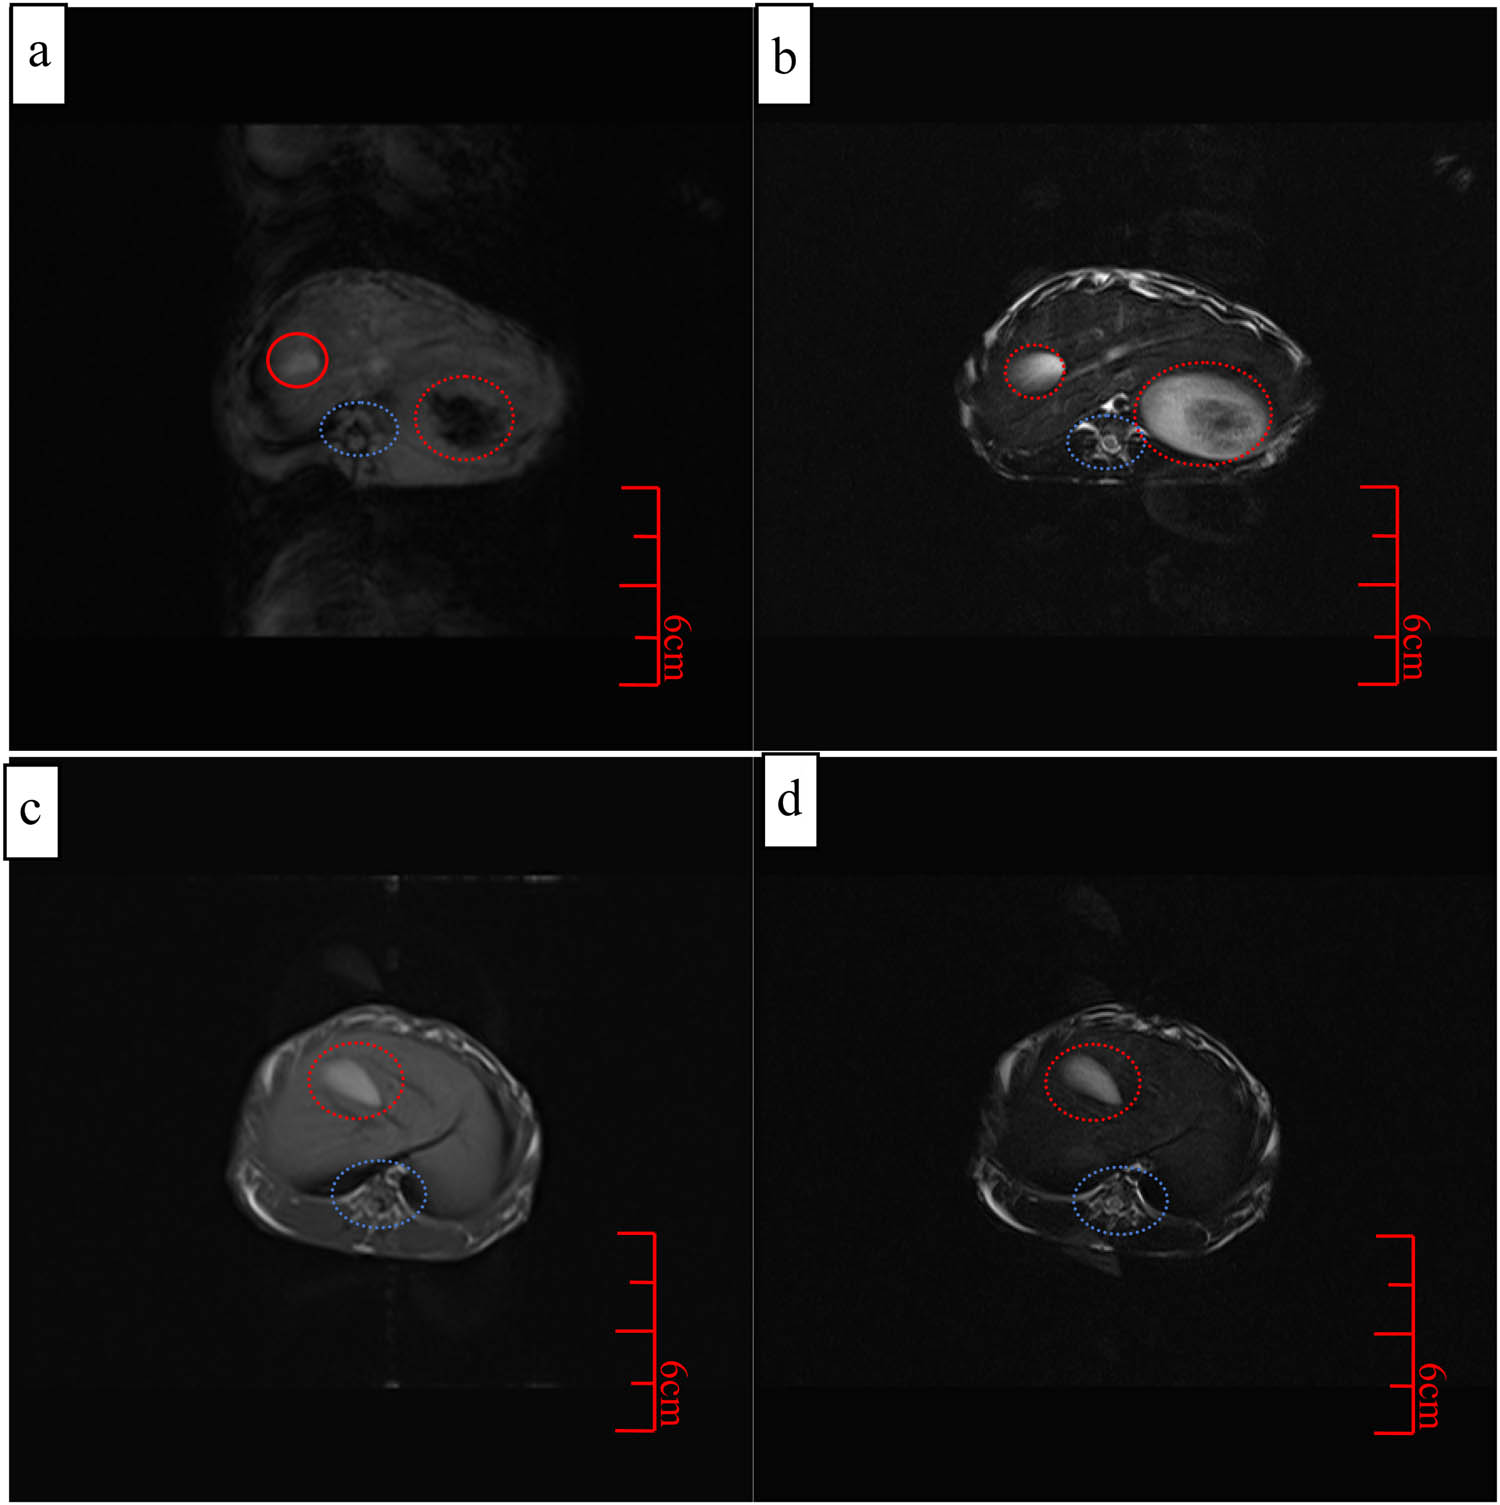

The liver as the region of interest was selected for observation pre-and post-injection of Fe3O4@DDT-PMAA MFs at a low dose (0.8 mg Fe kg−1) in transverse and longitudinal imaging. The T 1-weighted images became brighter and T 2-weighted images became darker when compared with the T 1 and T 2-weighted pre-contrast images (Figure 8). It can be clearly seen from the comparison of Figure 8a and b that the bright visual field increased significantly, where the area was not clear before injection was clearly visible after injection (in the red circle, hepatoma cells), in addition, other tissues were clearly visible (in the blue circle), which was mainly related to the higher r 1 value [44]. Furthermore, the background of Figure 8b was less visible, which may be related to the drug metabolism mainly in the liver. Similarly, T 2-maping imaging had similar results, the picture was clearer and the tissue was more obvious. More importantly, the background image became more blurred after administration than before, which indicated that it was more helpful for accurate diagnosis after administration. The results showed that Fe3O4@DDT-PMAA MFs owned the potential for simultaneous T 1 and T 2 contrast enhancement images, which can provide more comprehensive information and higher accuracy for image-guided diagnosis and treatment.

Simultaneous T 1- and T 2-weighted coronal images of Fe3O4@DDT-PMAA MFs in rabbit liver cancer, (a) pre-rejection for T 1 images; (b) after-rejection for T 1 images; (c) pre-rejection for T 2 images; and (d) after-rejection for T 2 images.